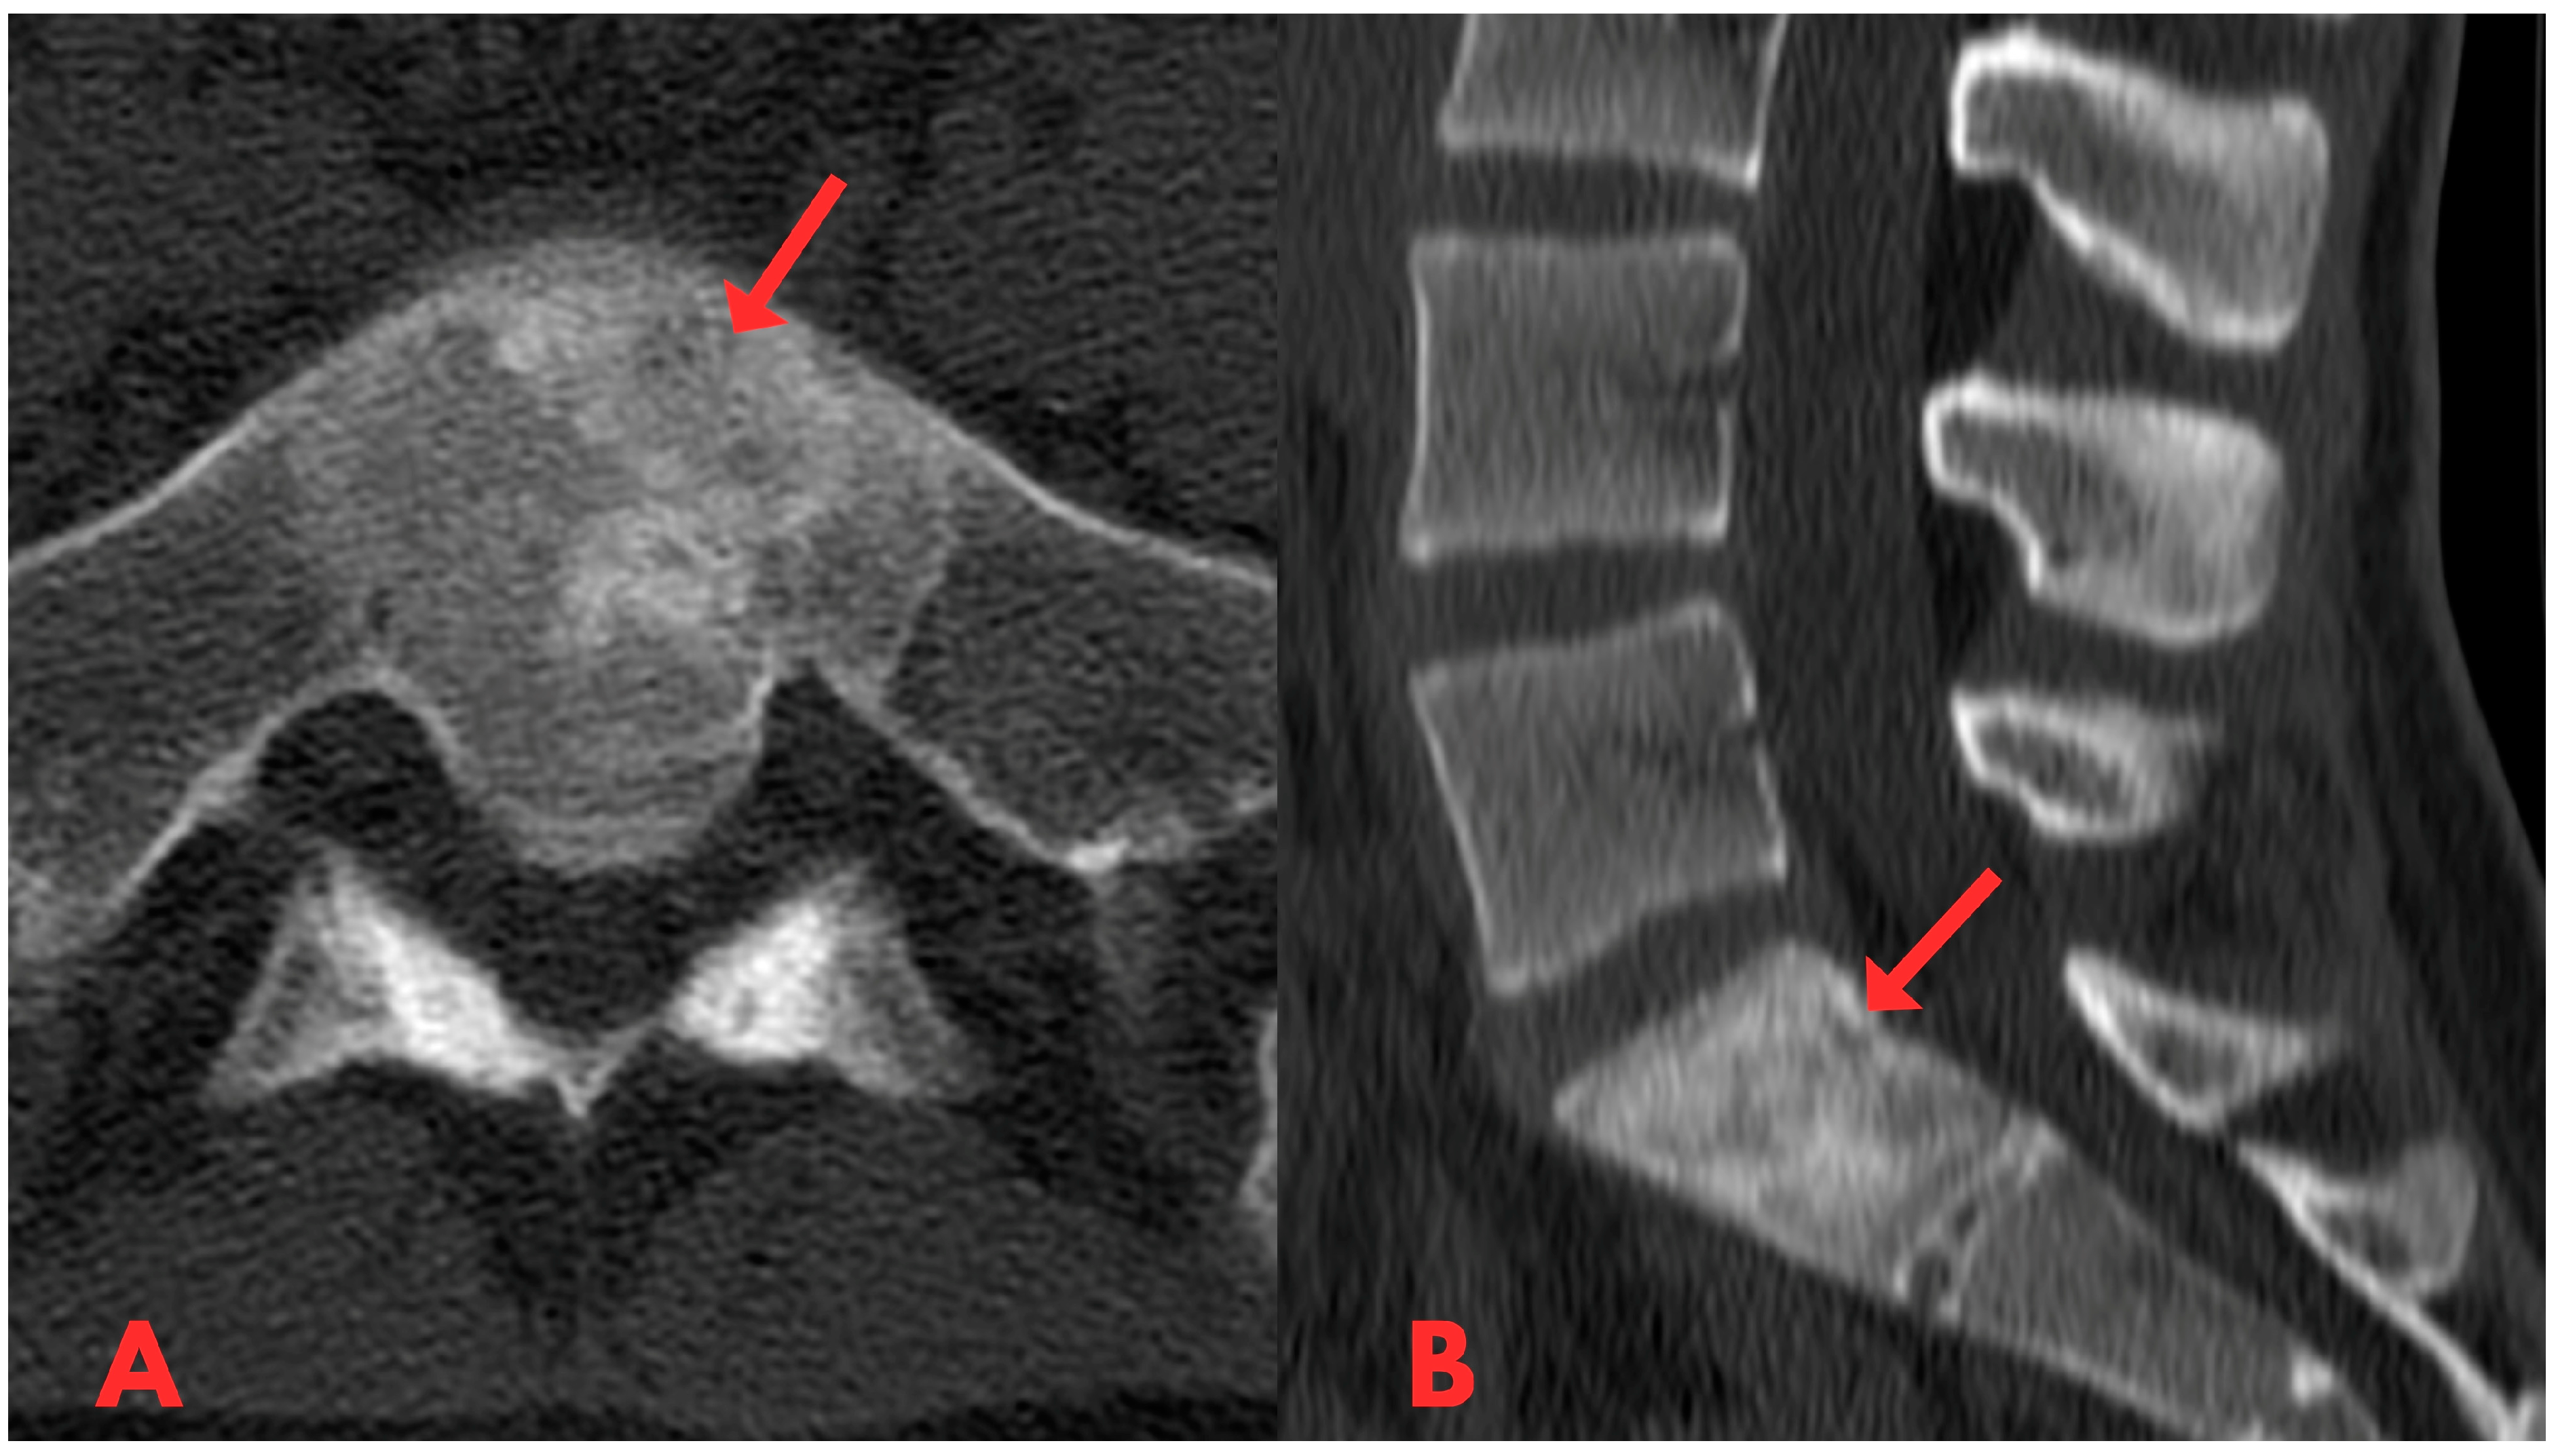

Initially, a CT examination of the lumbar spine was performed, which revealed heterogeneous sclerotic changes in the body of the S1 vertebra (Figure 1). Interpretation suggested possible post-traumatic changes in the S1 vertebral body; however, since the patient had no history of trauma, this diagnosis was ruled out.

Figure 1.

First CT examination of the lumbar spine axial (A) and sagittal (B) planes, showing heterogeneous sclerotic changes in the body of the S1 vertebra (red arrow).